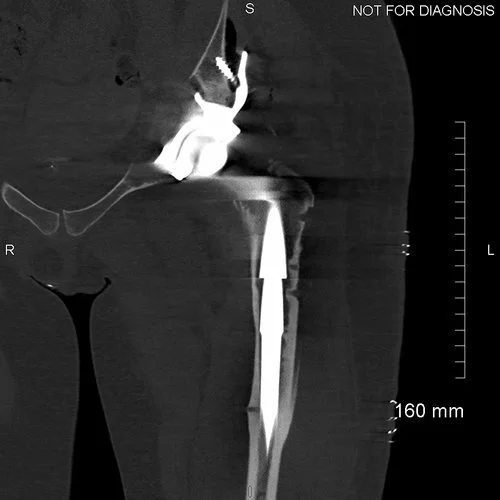

Coronal CT - This is used by the surgeon and the biomedical engineer to design the custom implant specifically to the patient’s acetabular bone stock. This CT demonstrates significant loss of bone stock relating to the left hip resurfacing.

3D CT reconstruction showing the hemipelvic defect.